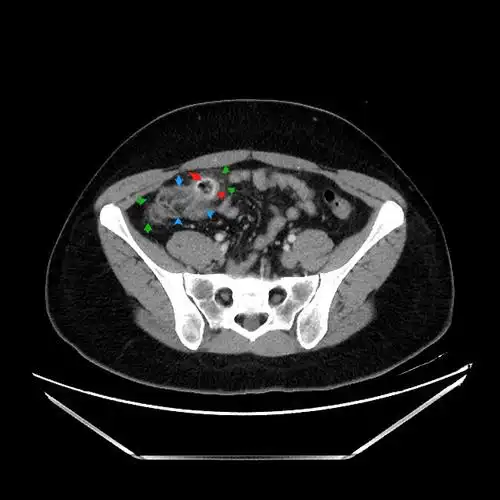

盲肠憩室炎ct表现分享,专科医生讲解,收藏学习!

容易被误诊的右下腹疼痛之盲肠憩室炎